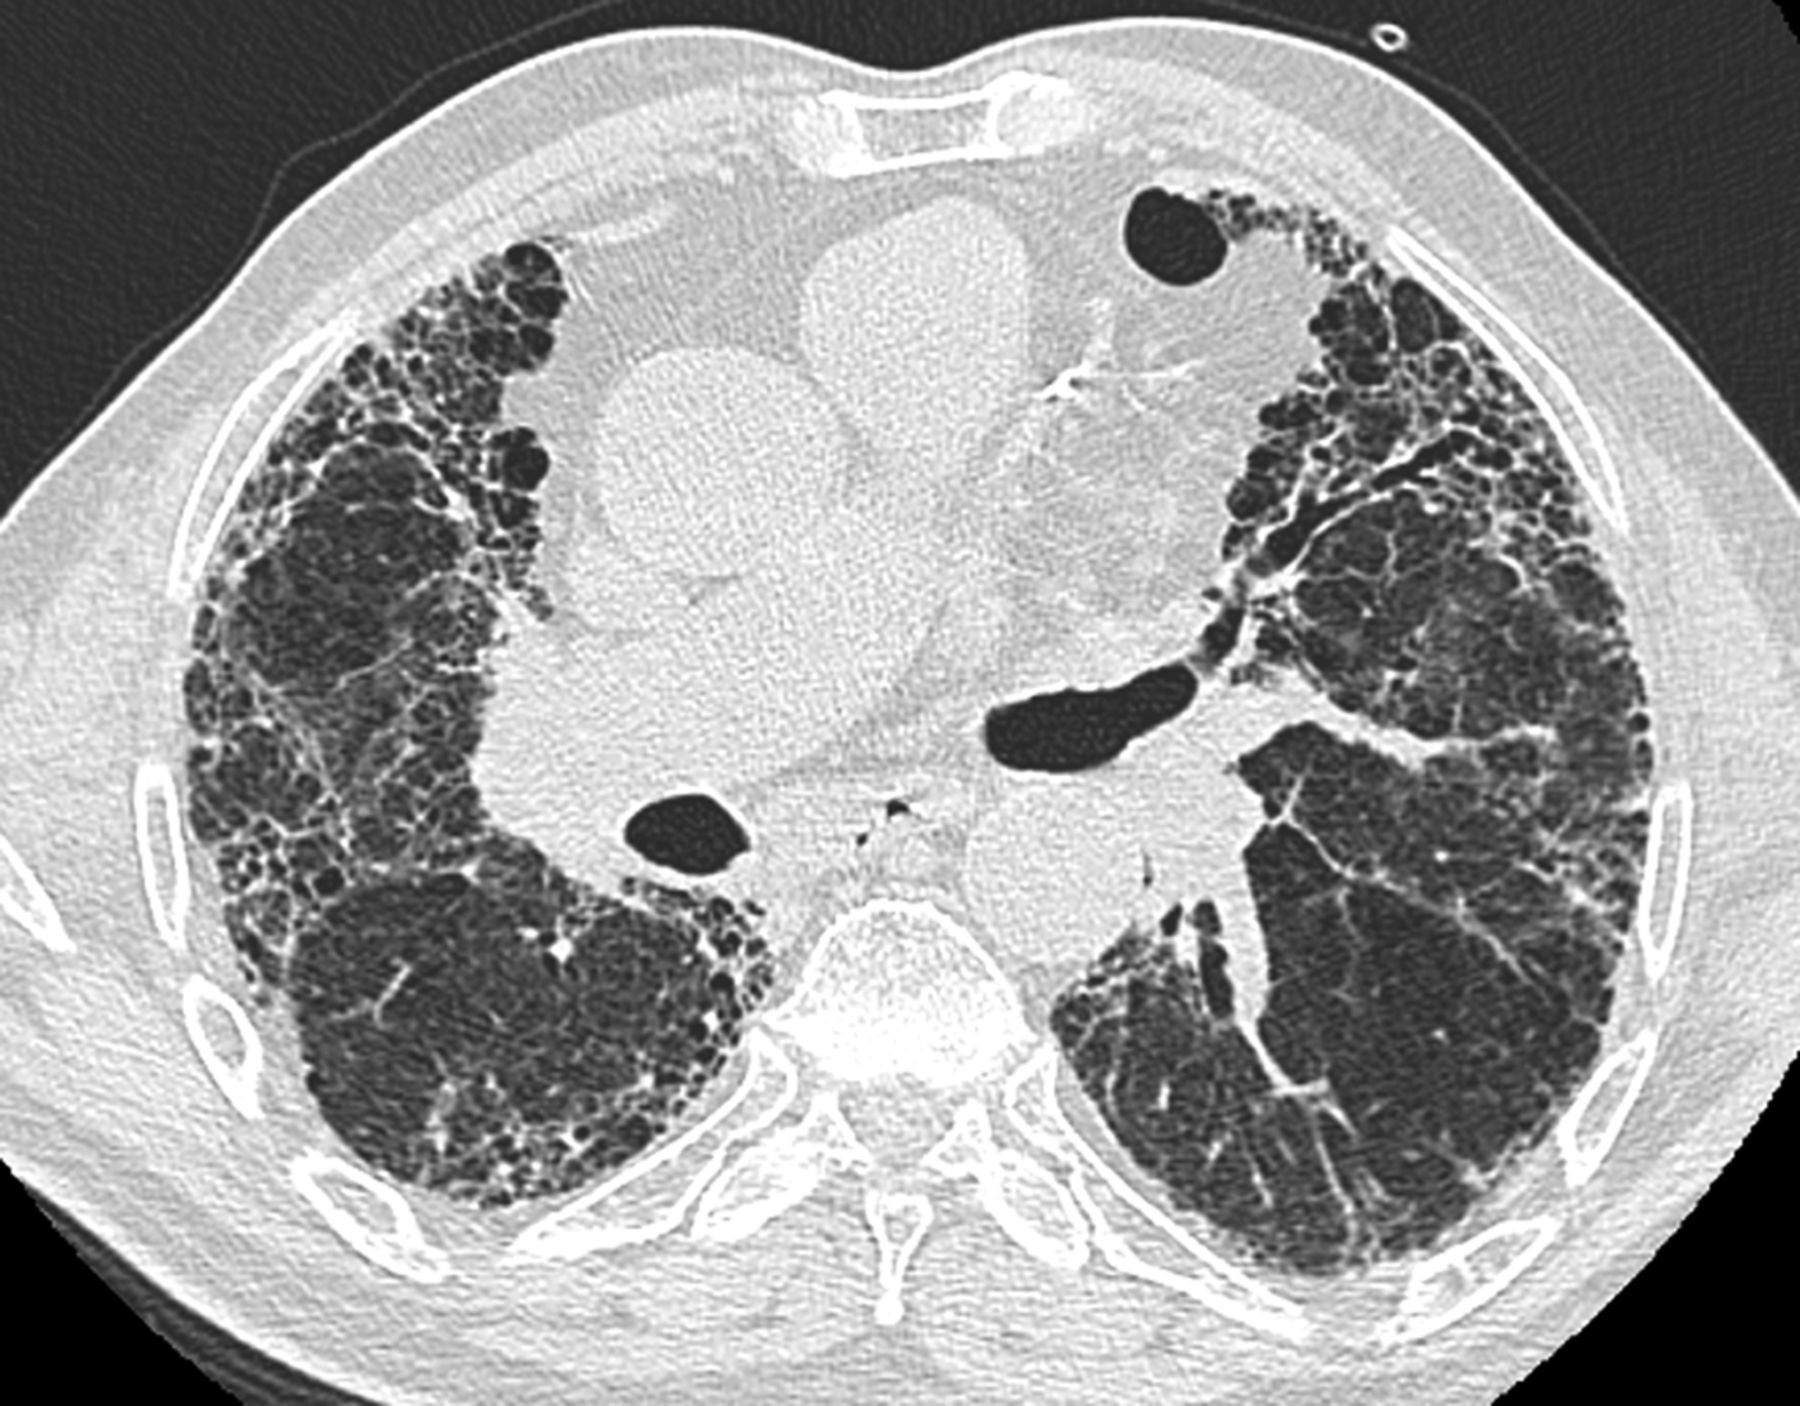

_雙肺肺纖維化的

_雙肺肺纖維化肺灶